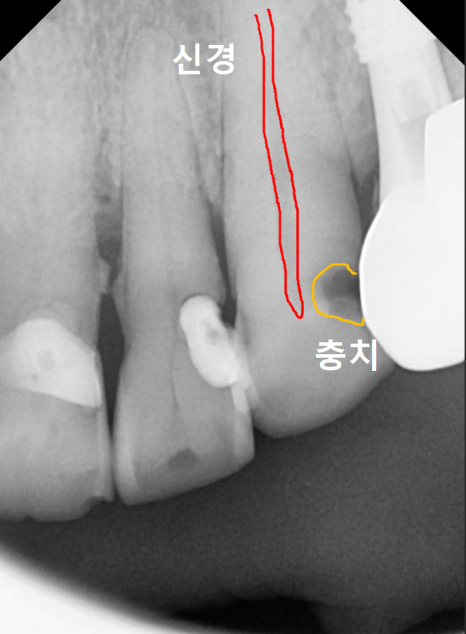

방사선 사진을 살펴보니,

충치가 신경까지 아주 가깝게

진행되어 있었는데요...

240223

이번에 문제가 생긴 앞니들은

신경치료 후 보철물을 연결하는

스플린트 형태로 제작하기로 계획했습니다.